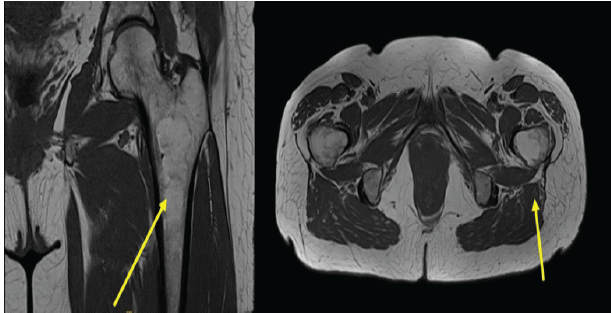

Further MRI of the pelvis and hips demonstrated a well-circumscribed intramedullary lesion with homogeneous high signal intensity on T1-weighted sequences and complete signal suppression on fat-suppressed images (Fig. 4a). No surrounding marrow edema, cortical breach, or contrast enhancement was identified (Fig. 4b). These findings were diagnostic of an intramedullary lipoma. No features suggestive of malignant transformation were present.

Figure 4: (a) Coronal T1-weighted magnetic resonance imaging (MRI) of the pelvis demonstrating a well-circumscribed intramedullary lesion within the proximal left femur exhibiting homogeneous high signal intensity consistent with fat content (arrow). (b) Axial T1-weighted MRI confirming central intramedullary location with preserved cortical margins and no surrounding marrow edema or soft-tissue extension (arrow).